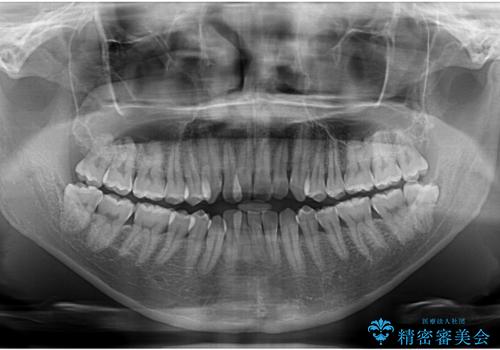

- 前歯のデコボコ(叢生)と、少し前に出た口元を気にされて来院された患者さまです。

診査の結果、上下顎ともに歯が並ぶスペースが不足しており、上下の前歯が噛み合わない**オープンバイト(開咬)**の状態でした。

歯をすべて並べようとすると口元がさらに前に出てしまうため、上下左右の第一小臼歯を抜歯してスペースを確保し、デコボコと突出感の両方を改善する治療計画を立てました。

舌を前に押し出す癖(舌突出癖)があり、後戻りやオープンバイトの再発防止のため、MFT(口腔筋機能療法)も併用しています。